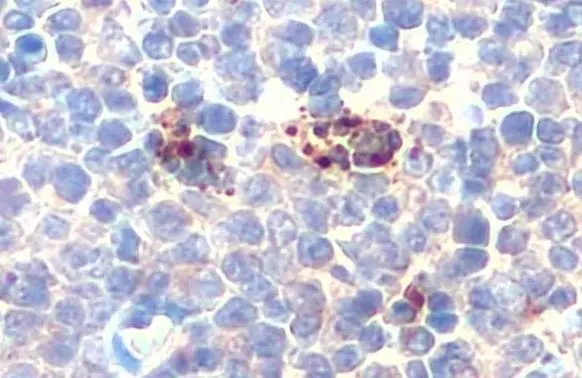

ApplicationsWestern Blot, ImmunoHistoChemistry, ImmunoHistoChemistry Paraffin

- ApplicationsWestern Blot, ImmunoHistoChemistry, ImmunoHistoChemistry Paraffin

- Scientific DescriptionThis gene encodes a 140 kDa protein that is stored in the alpha-granules of platelets and Weibel-Palade bodies of endothelial cells. This protein redistributes to the plasma membrane during platelet activation and degranulation and mediates the interaction of activated endothelial cells or platelets with leukocytes. The membrane protein is a calcium-dependent receptor that binds to sialylated forms of Lewis blood group carbohydrate antigens on neutrophils and monocytes. Alternative splice variants may occur but are not well documented. [provided by RefSeq, Jul 2008]